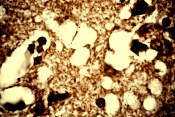

Tejido cerebral afectado con el prion del CJD |

Los pacientes desarrollaron un daño cerebral asociado al CJD (del tipo no ligado al BSE, bovine spongiform encephalopathy, o encefalopatía espongiforme bovina), pero los científicos creen que puede haber una causa genética.

Recién cuando las víctimas fallecieron se pudo constatar el típico tejido del cerebro con huequitos, convertido casi en esponja, que se suele encontrar en los afectados con el CJD.